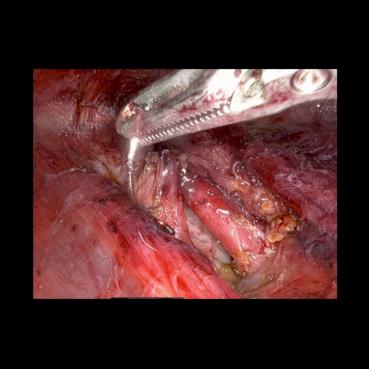

The medical images considered are obtained from a video of a surgery called Bilateral Axillo-Breast Approach (BABA) robotic thyroidectomy, approved by the Research Ethics Committee of Seoul National University Bundang Hospital (B-2504-969-701). This is a thyroid surgery method that is representative of remote access surgery. Clinically, BABA surgery is well known for its superior cosmetic effects and lower complications than conventional thyroidectomy. This surgical method creates surgical incisions in both axillae and both areolas and uses the da Vinci robot to perform the surgery. The surgical video is recorded during the surgery, and the high-resolution images captured are analyzed to develop meaningful clinical studies. Therefore, encoding a high quality of image into a quantum circuit may be significantly important for the future of clinical studies.

The image Fig. 4(a) has a resolution of 636×842636842636\times 842636 × 842 pixels as cropped from a 1280×72012807201280\times 7201280 × 720 image, which shows both human organ and surgical tools. We zero pad the image to one with 1024×1024102410241024\times 10241024 × 1024 pixels as shown in Fig. 4(b). Since the new image has 1024×1024102410241024\times 10241024 × 1024 pixels, the required number of qubits for Fig. 4(c),(d) is 20. On the other hand, for the images Fig. 4(e),(f), which correspond to the case of blockwise image encoding strategy, we divide the new image into 512×512512512512\times 512512 × 512 four images. Thus, 18 qubits are required for the simulated images in Fig. 4(e),(f).

Since the image is colored, we apply the encoding strategies three times by dividing a 3d-array of pixels involving RGB colors into three 2d arrays. Thus, for Fig. 4(c),(d), which is the case of encoding the whole image, 3 circuits are used, while 12 circuits are used for Fig. 4(e),(f) since the image are partitioned into four blocks.

We performed similar numerical simulations for more images taken at different frames. Fig. 5 compares the original zero-padded images, the corresponding reconstructed images using FAQPIE with and without the combination of two compression techniques with the same parameter setting as in Fig. 4. A similar observation is made that encoding the images with the two compression techniques results in more efficient FAQPIE with reasonable surgical details and lowered gate counts, as summarized Table 3.

Figure 4: We zero pad the original medical images (a) to one of size 1024×1024102410241024\times 10241024 × 1024 (b). Then, we encode the zero-padded surgical image using FAQPIE for the simulation (c). The figures (d), (e), and (f) are obtained with one of the compression techniques or both in Section II.2. For short, we call compression of UCRs CUCR and image partition IP.

Figure 5: Comparison of original medical images (left), the corresponding reconstructed images via FAQPIE with no compression technique (middle) and the two compression techniques applied as in Fig. 4 (right).